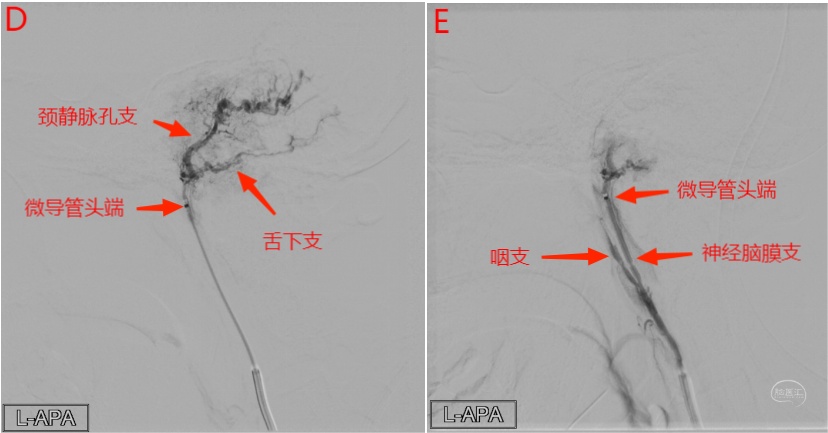

图22 左侧咽升动脉神经脑膜支微导管超选侧位造影(D)显示供血动脉舌下支和颈静脉孔支,颗粒栓塞后经左侧咽升动脉神经脑膜支微导管超选侧位造影(E)显示病变血供明显减少,造影剂返流进入咽升动脉主干和咽支。